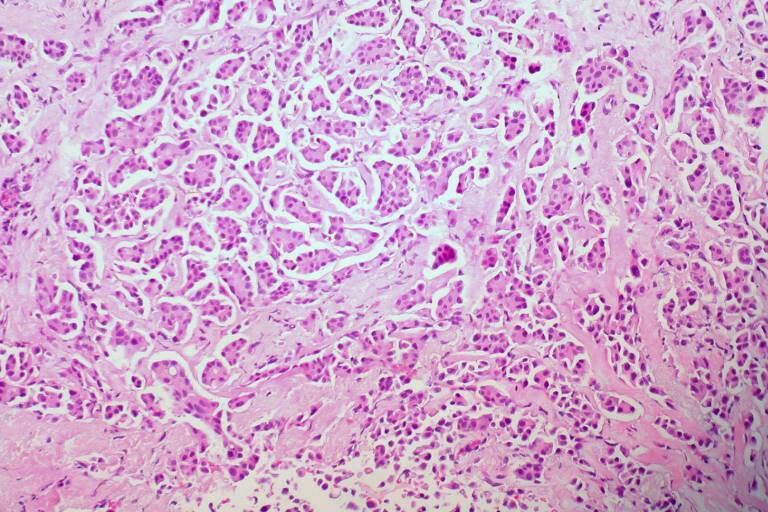

breast cancer - A new revolutionary test for detecting ovarian and breast cancer, which could potentially measure future cancer risk, is being developed by researchers from UCL's Institute for Women's Health. The research is led by Professor Martin Widschwendter (UCL Institute for Women's Health, University of Innsbruck and the European Translational Oncology Prevention and Screening Institute) and is funded by The Eve Appeal and the European Research Council. The test uses a single sample from routine cervical screening to detect or predict the risk of four cancers, including ovarian and breast cancer and may identify up to 30% more women with a high risk for breast or ovarian cancer than current genetics-based tests. The research involved assessing samples from over 3,000 women from 15 European centres. The researchers then used cervical screening samples as a surrogate tissue to measure marks on the DNA (DNA methylation) of cervical cells and found that they can be specifically related to whether someone has breast or ovarian cancer. DNA methylation can be thought of as the 'software' of our cells as it determines how our cells should read and act on instructions in the DNA (the 'hardware') . As people go through life, their environment and lifestyle is constantly updating the 'code' to their software, and so the DNA methylation changes.